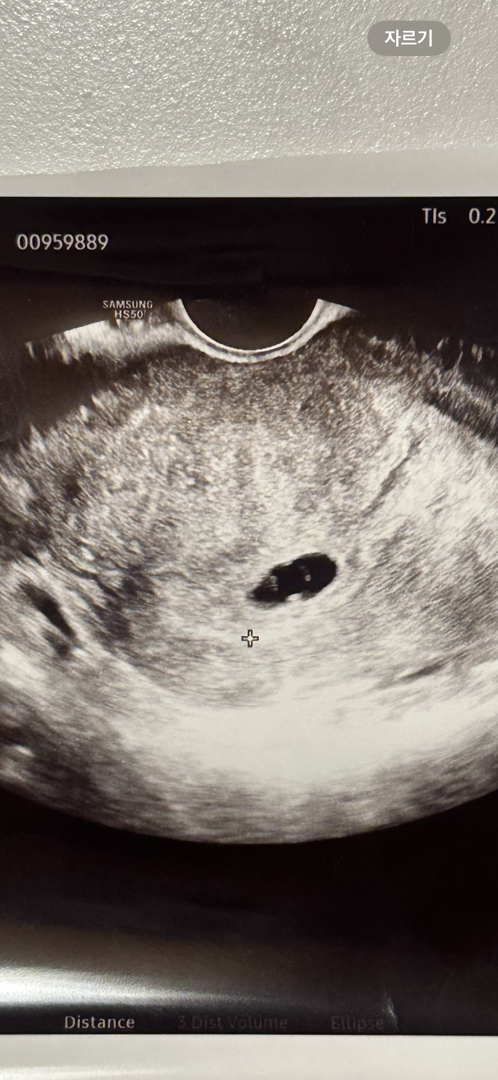

6주0일 난황이너무 크데요..

11월6일 임신확정 4주6일 0.61cm 다낭성이라 생리주기도 불규칙해서 자연임신이 되어 정말 기뻤어요. 난황이랑 심장이 보일까해서 오늘 초음파 보러갔어요 . 오늘로 6주0일 난황이 너무 크고 , 첫 초음파 사이즈에 비해 아기집도 작고 아기도 안보인다고 말씀하시네요. 심장반짝임도 없고,, 초음파는 일주일 뒤 오라고 하시는데 피검사 오늘 , 다음주월요일 피검사 예정입니다. 자연유산이 될 수도 있다고 하시는데 너무 걱정되네요.. 난황크면 예후가 좋지않던데,. 조언부탁드려요.